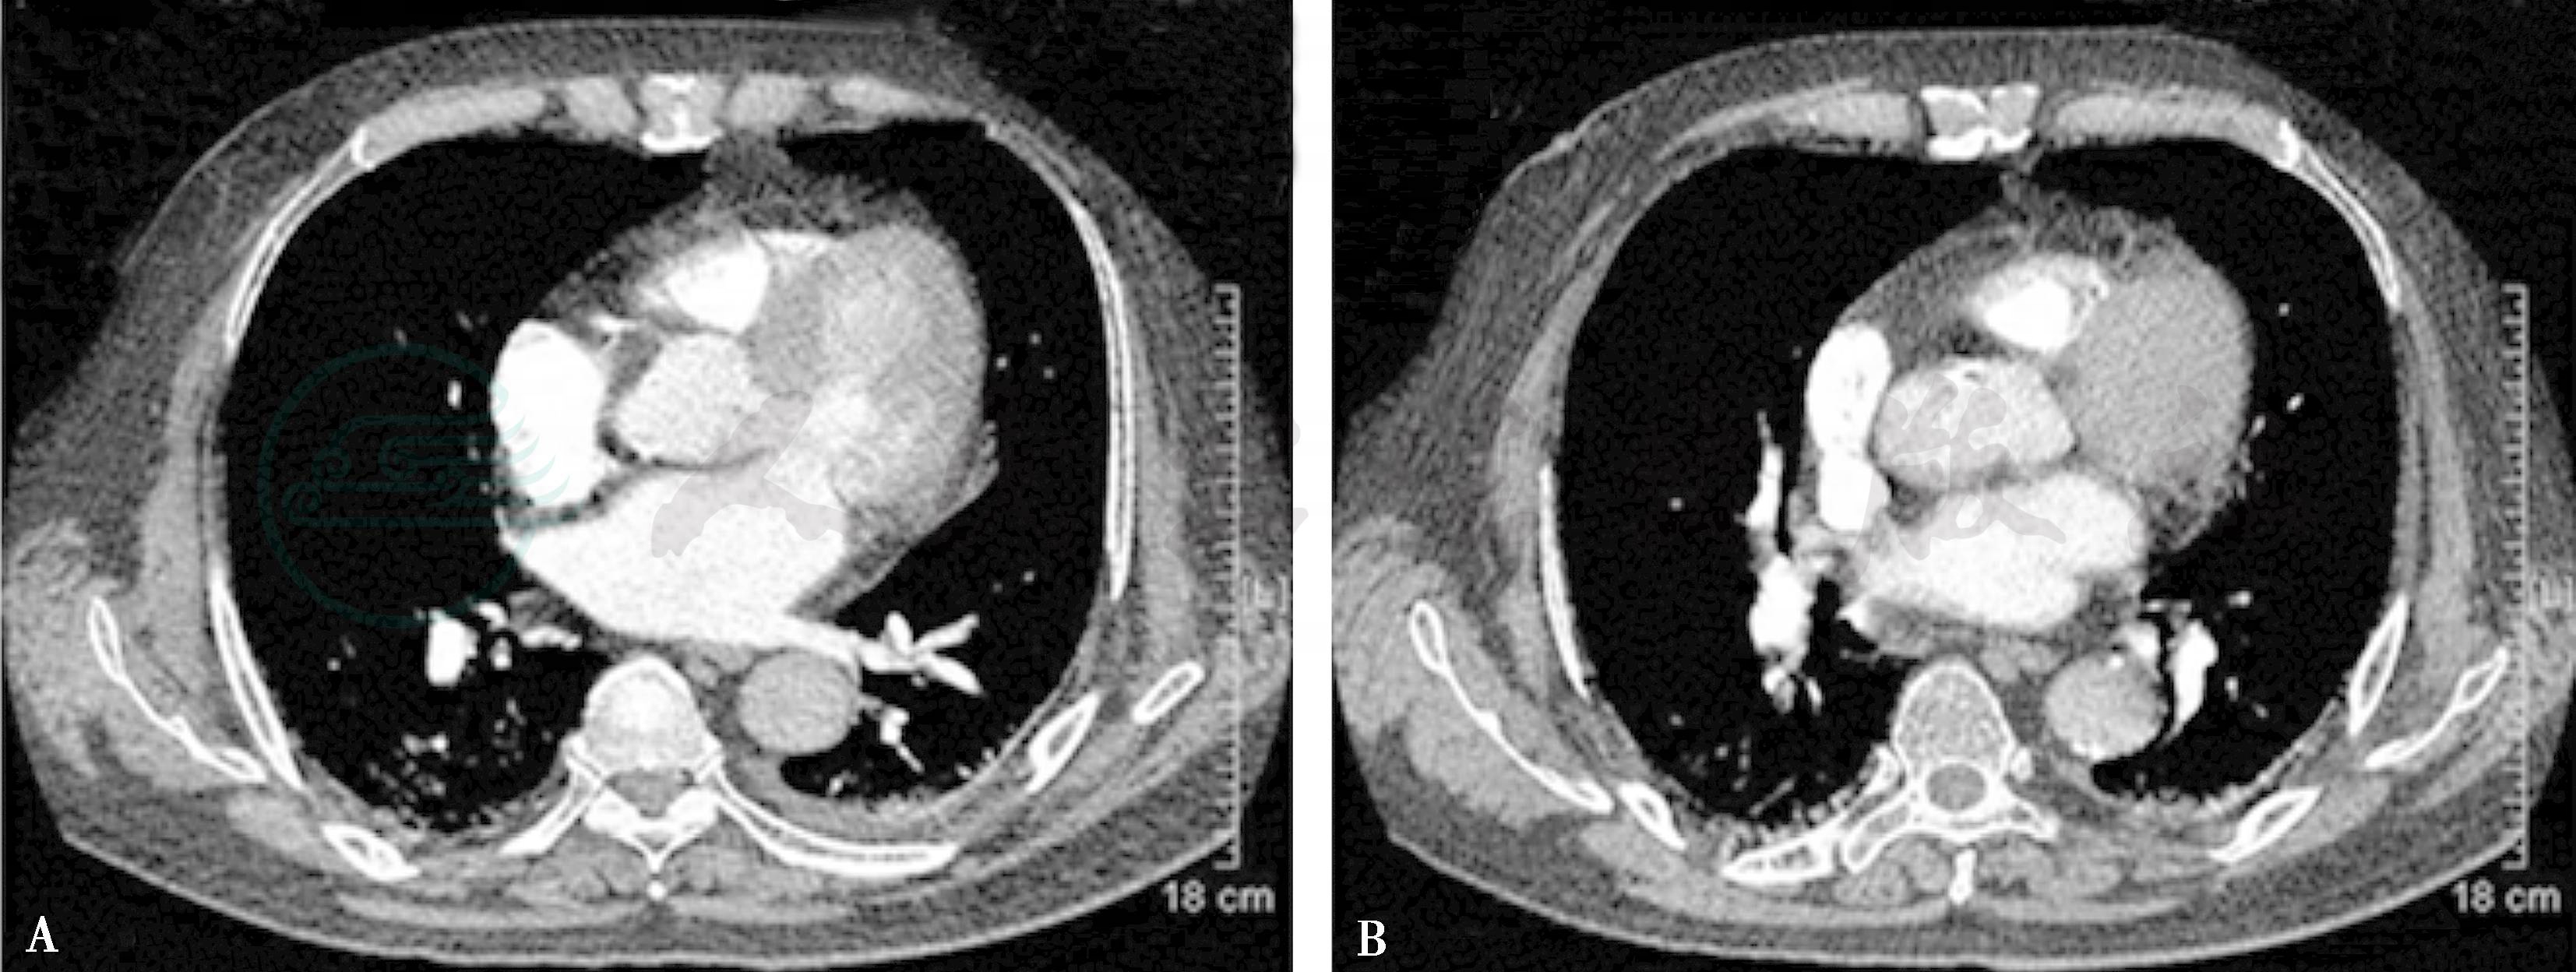

图2 2013年3月31日肺动脉CTA

双肺动脉分支栓塞较前好转

A.左下肺动脉充盈缺损基本消失;B.右肺叶分支动脉充盈缺损较前明显减少